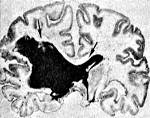

I61.5 Внутримозговое кровоизлияние внутрижелудочковое